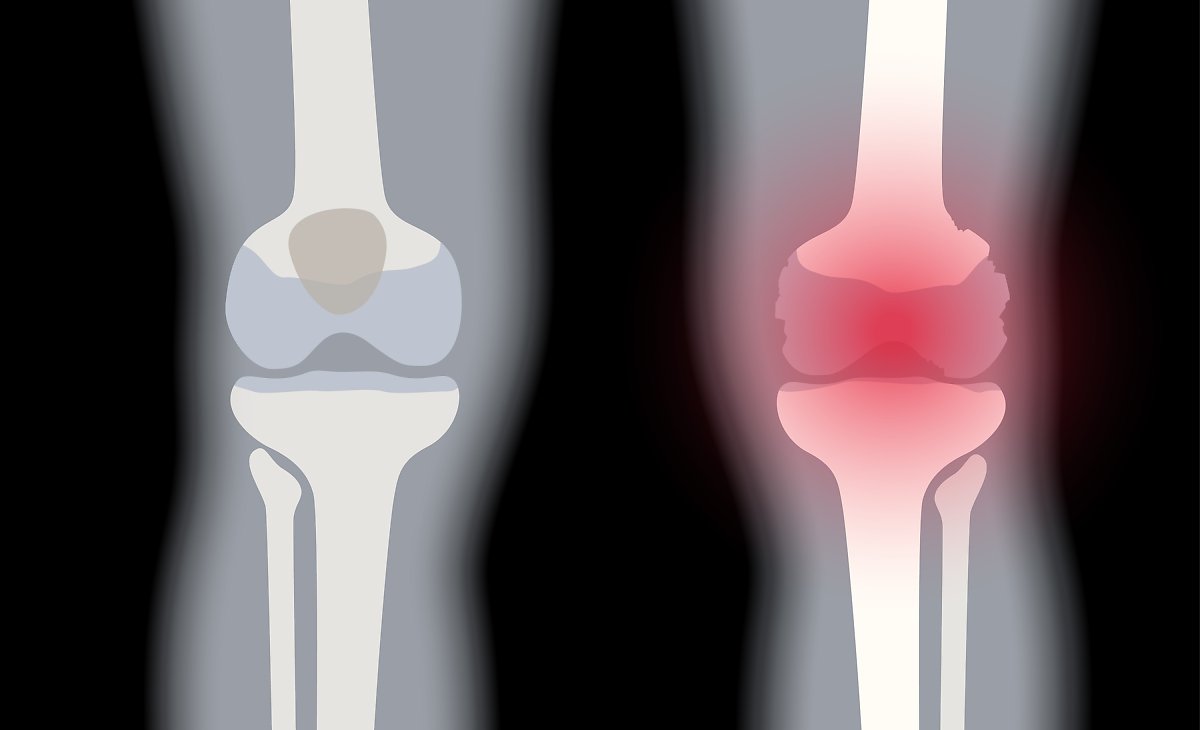

활막에 염증이 생기면 주변 연골과 뼈로 염증이 확산되며 관절 통증, 열감, 압통과 함께 부종이 발생합니다. 보통 양측성으로 나타나며 손목·팔꿈치·무릎·손가락·발가락 등에서 흔히 통증을 호소합니다.

5. 관절 붓기

관절 주변 피부가 붉게 변하는 현상으로, 염증으로 혈관이 확장되어 혈류가 증가하면서 발생합니다. 손·발 관절 부위 피부가 붉게 보이면 염증성 관절염을 의심할 수 있는 시각적 신호가 됩니다.